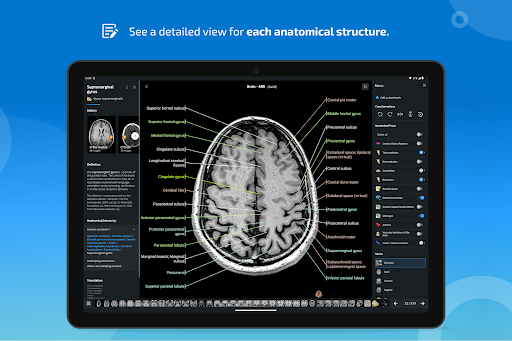

-In the details view of an anatomical structure related terms are now displayed

-Within the details view of an anatomical structure, a pin now points the related structure in all present images

- “Filter by”, in the details view you can now filter the images containing the anatomical structure by modality